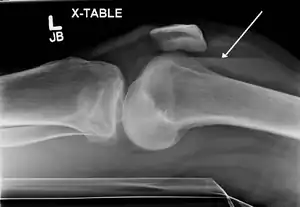

In all injuries to the tibial plateau radiographs (commonly called x-rays) are imperative. Computed tomography scans are not always necessary but are sometimes critical for evaluating degree of fracture and determining a treatment plan that would not be possible with plain radiographs.[5] Magnetic Resonance images are the diagnostic modality of choice when meniscal, ligamentous and soft tissue injuries are suspected.[6][7] CT angiography should be considered if there is alteration of the distal pulses or concern about arterial injury.

Lipohemarthrosis (presence of fat and blood from bone marrow in the joint space after an intraarticular fracture) seen on X-ray in a person with a subtle tibial plateau fracture

Lipohemarthrosis due to a tibial plateau fracture